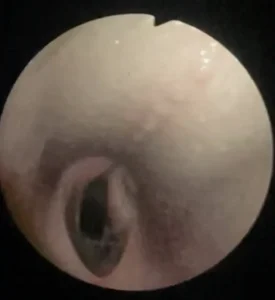

- Upper airway endoscopy to detect possible respiratory pathologies.